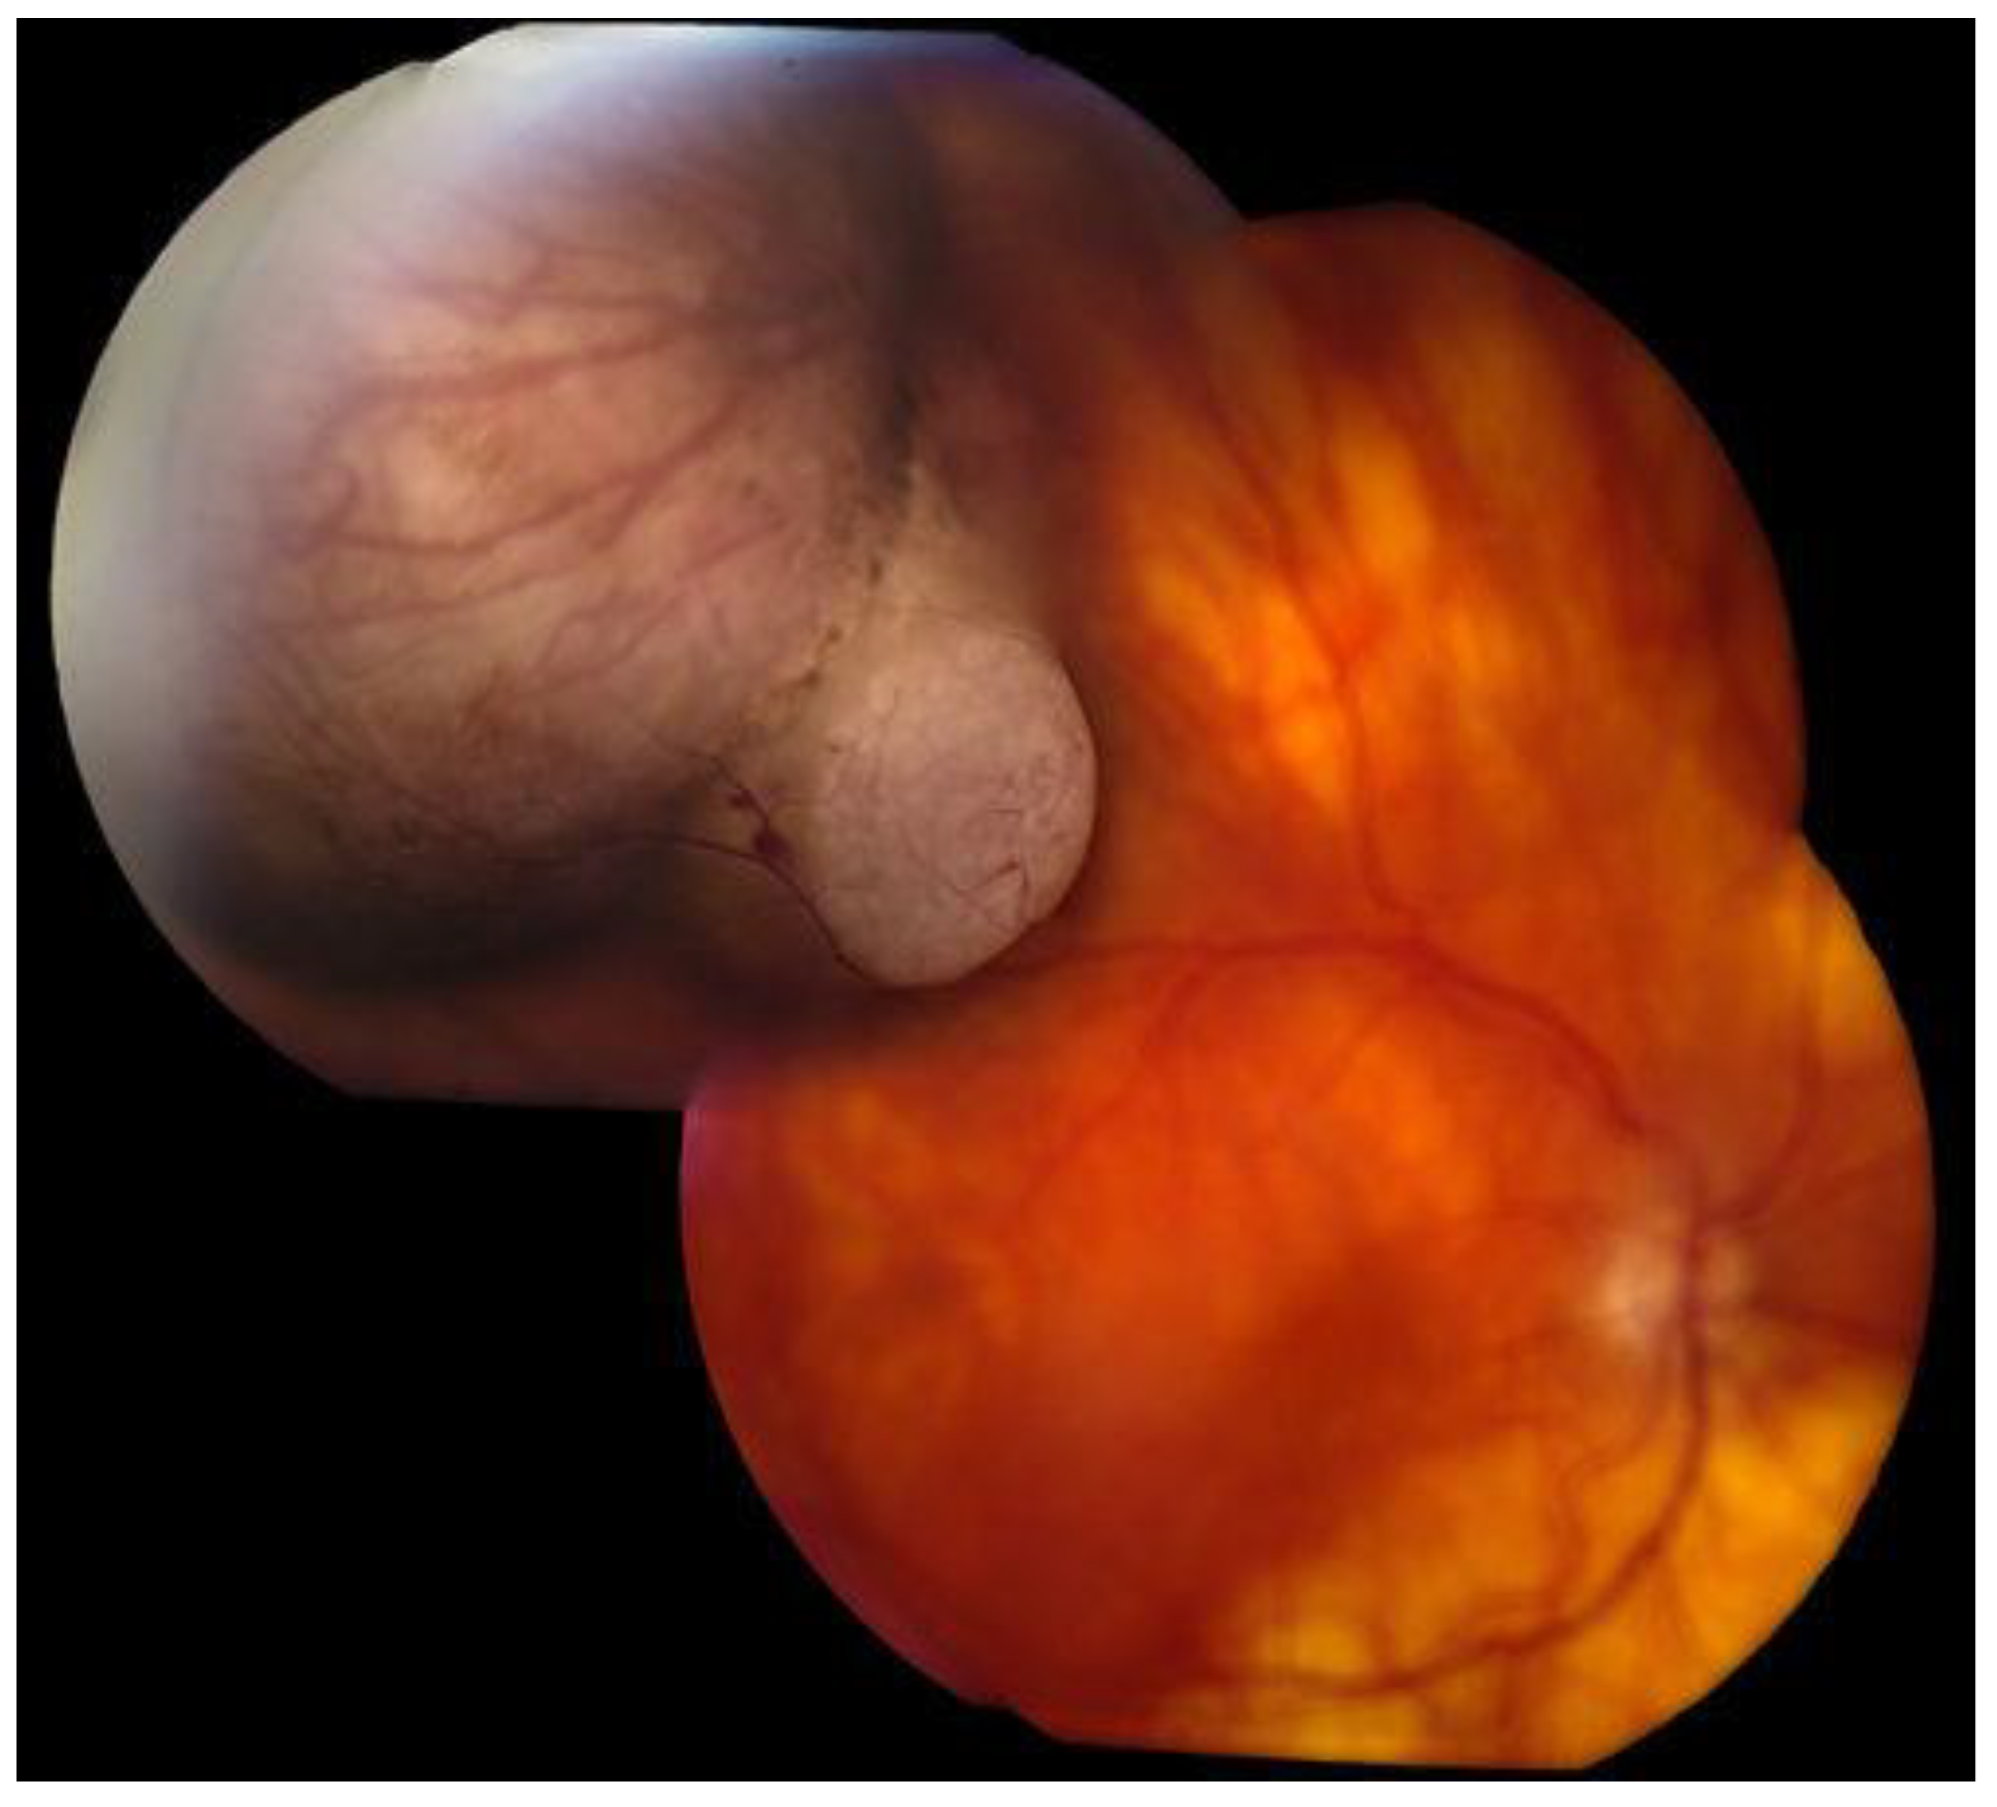

6. History

7. Physical Examination and Evaluation

8. Differential Diagnoses